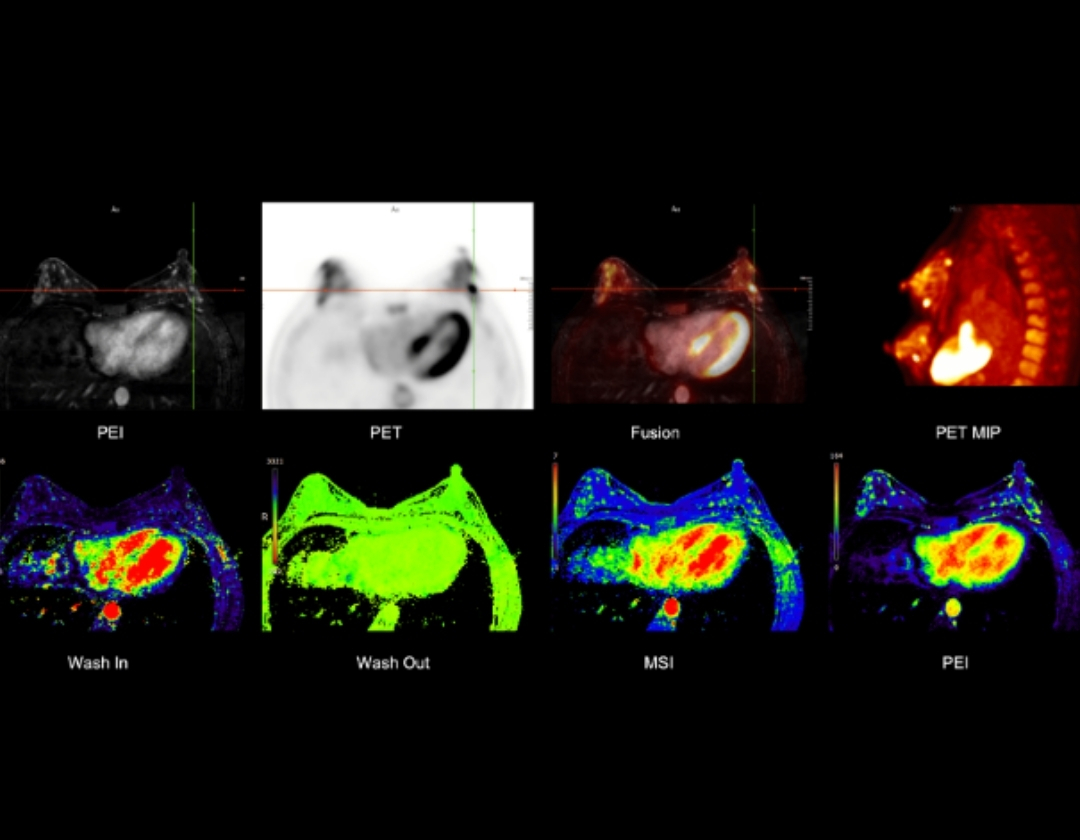

Multi-parametric PET/MR for Comprehensive Breast Evaluation